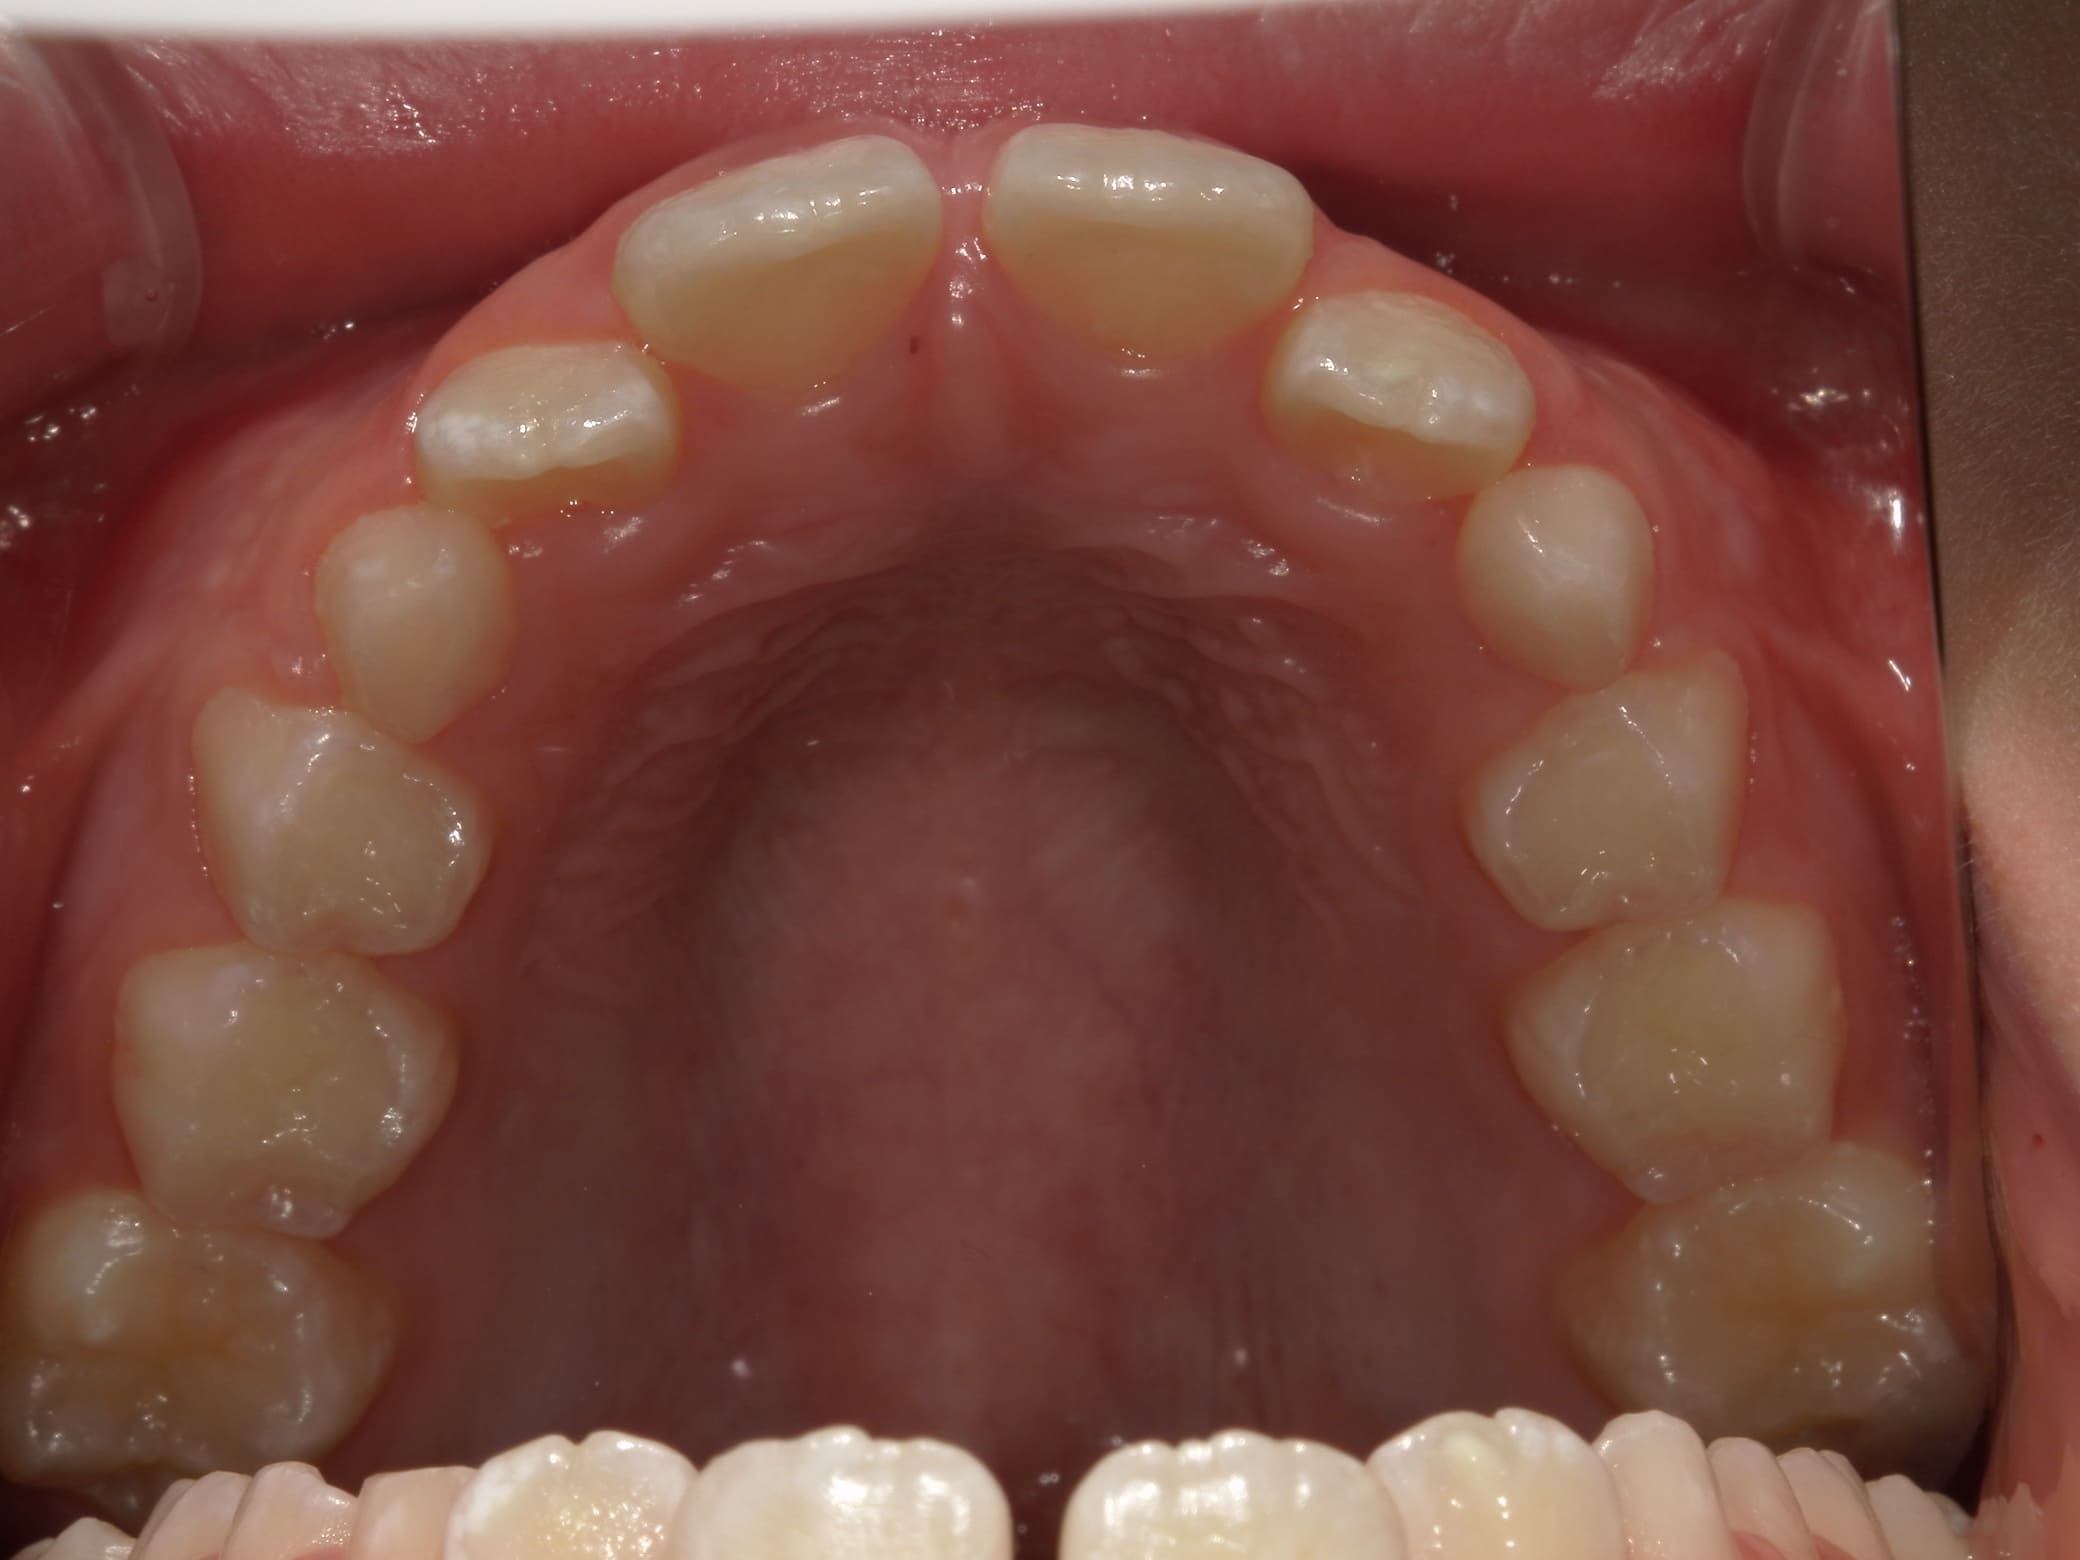

| 年齢・性別 | 8歳11ヶ月の男児 |

|---|---|

| 主訴 | 上顎の永久歯の位置がおかしいとのことで来院。萌出していない右上の前歯の状態に不安を抱えられていました。 |

| 治療期間・回数 | 約3年2ヶ月 |

| 費用 | 440,000円(税別) |